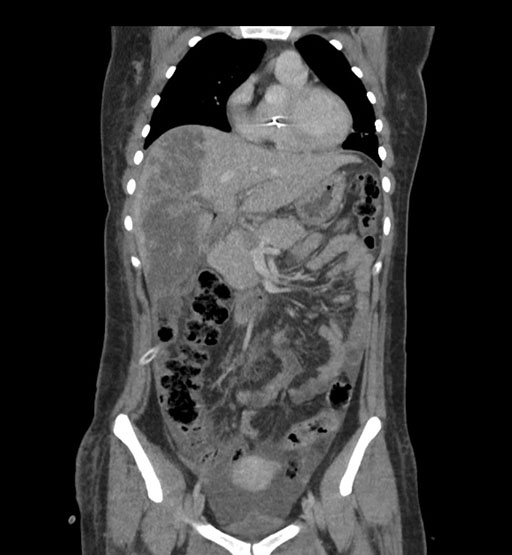

Coronal Venous